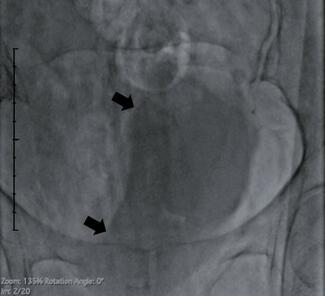

A 73-year-old man with history significant for paroxysmal atrial fibrillation on apixaban underwent percutaneous coronary intervention (PCI) of the left anterior descending artery via transradial access.